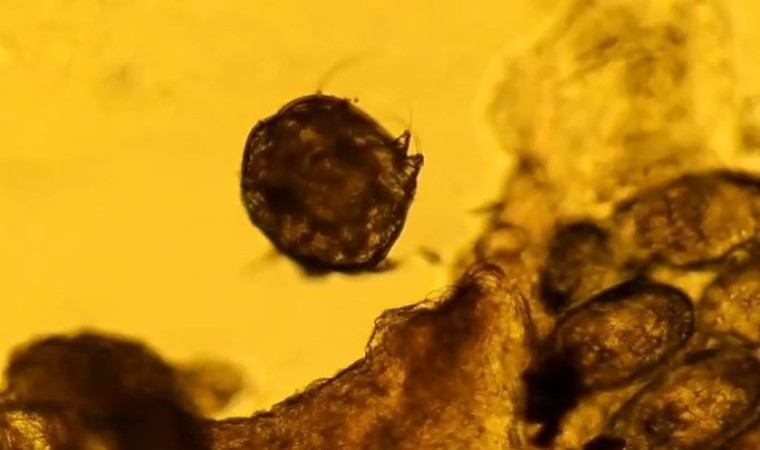

Uyuz hastalığının tanı ve tedavi sürecine değinen Doç. Dr. Mustafa Tosun, “Özellikle kaşıntı yani en önemli geceleri özellikle ortaya çıkan bir kaşıntı söz konusu. Hastanın hayat kaidesini etkiler. Yani gece uykudan uyandırır özellikle. Çünkü parazit derimizde yaşıyor. Derimizde tüneller oluşturup orda bir reaksiyon deride bir reaksiyon ortaya çıkartıp oda kaşıntı ve alerjik reaksiyonları ortaya çıkarmakta. Aynı zamanda hem el parmak arası, el bilekleri, ayak bilekleri yine özellikle karın bölgesi, yine erkeklerde genital bölge, kadınlarda meme başı gibi alanları tutmakta ve orda popüler lezyonlar dediğimiz kabarcıklara özellikle kaşıntılı kabarcıklara neden olmakta. Hem bu şekilde hem özellikle etrafında kaşınan varsa özellikle aynı evde yaşayanlarda kaşıntı varsa bu da tabi hasta için uyarıcı olmalı. Yine sıcakla özellikle geceleri artar. Yine banyoda özellikle sıcakla artar. Kaşıntı olduğu zaman özellikle hastalarımızın uyuz açısından dikkatli olmaları gerekiyor ve mutlaka bir sağlık merkezine başvurmaları gerekiyor. Mikroskopla bir sürüntü alıyoruz deriden çok basit yani öyle bir gelişimsel bir şey değil ve onu 5 10 dakikalık bir süreçte tanıyı koyuyoruz. Aynı zamanda tabi klinik belirtilerde önemli biz deri muayenesi de yapıyoruz” ifadelerine yer verdi.